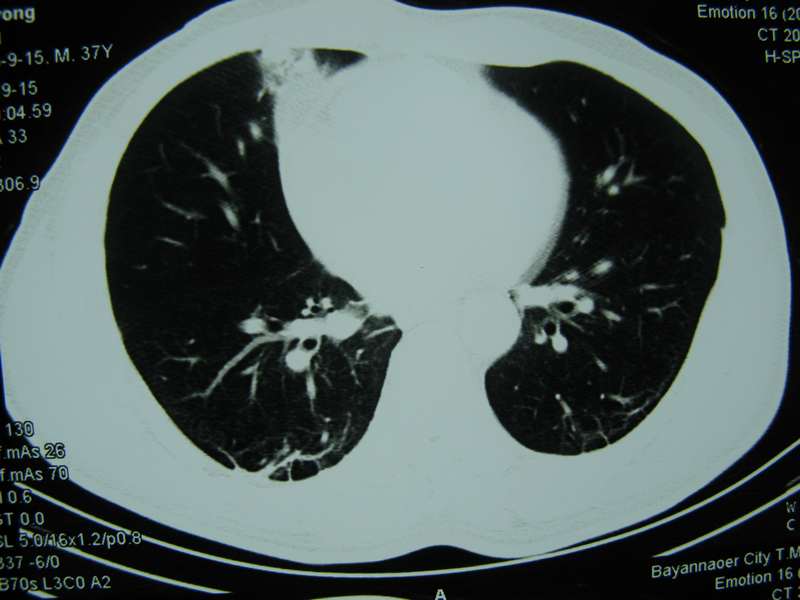

男,37岁,主述胸疼厉害,无咳嗽,无发热,血象也不高,病灶内ct值脂肪密度,右侧胸腔内少量积液,同道们考虑什么?谢谢!

脂肪垫,右下肺感染,少许积液是症状所在

纵膈脂肪堆积,右肺慢性炎症。

两肺下叶基底段纤维灶,右肺下叶基底背侧相应胸膜肥厚,右肺中叶内侧段部分不张。前中下纵隔团块状脂肪影,随访除外胸腺脂肪瘤。